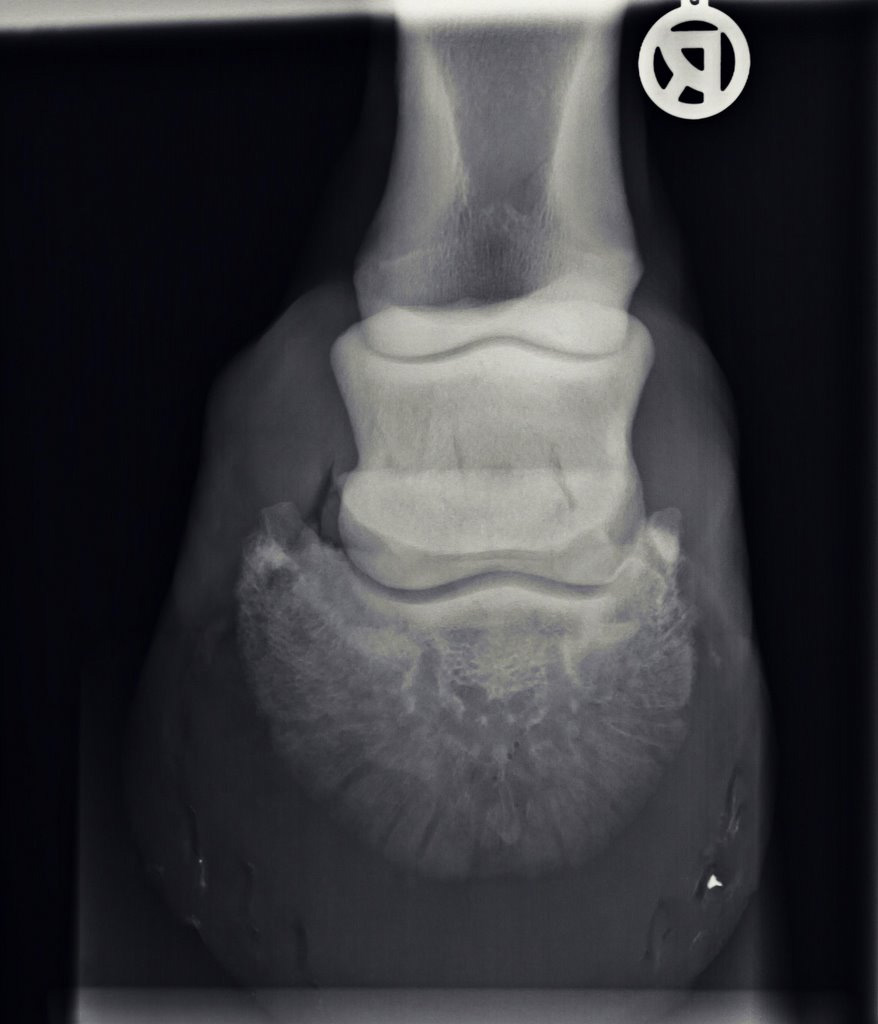

Illustrative Mindeststandardaufnahmen zur Beurteilung nach dem Röntgenleitfaden: